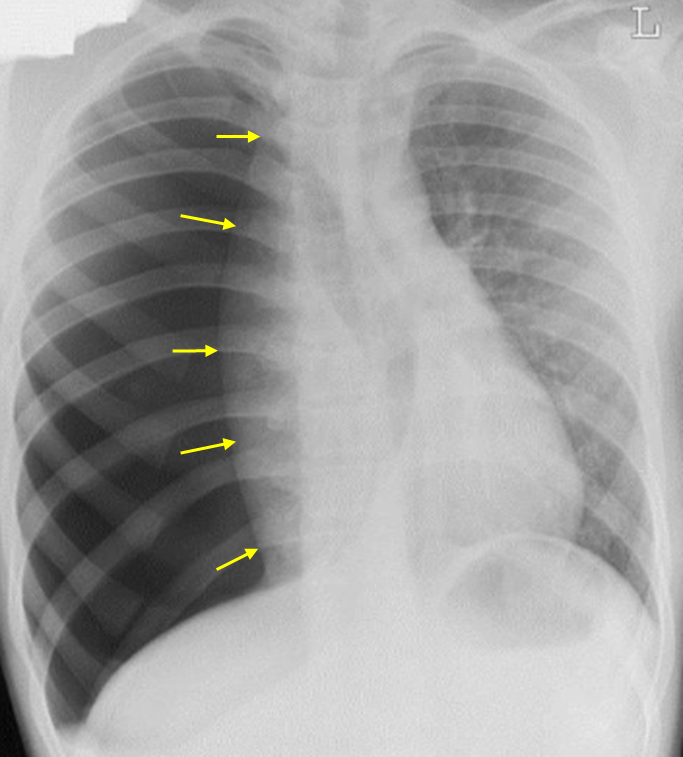

Img | CXR: Rt. pneumothorax, mediastinal shift and tracheal deviation to Lt. |

• 현재 V/S이 불안정하며 경정맥 확장까지 동반되므로 긴장성 기흉으로 이행되었음을 추정할 수 있다. 실제로 CXR 상에서도 우측 폐야에 pulmonary vascular marking이 하나도 보이지 않으므로 기흉을 진단할 수 있고, mediastinum과 trachea가 왼쪽으로 shifting 되어 있으므로 긴장성 기흉을 진단할 수 있다.

검사소견 | • CXR: Pleural line 보임, vascular marking이 보이지 않음 |

긴장성 기흉 | • V/S unstable • CXR: Mediastinal shift • 즉각적인 바늘 감압 → 이후 흉관 삽입 |